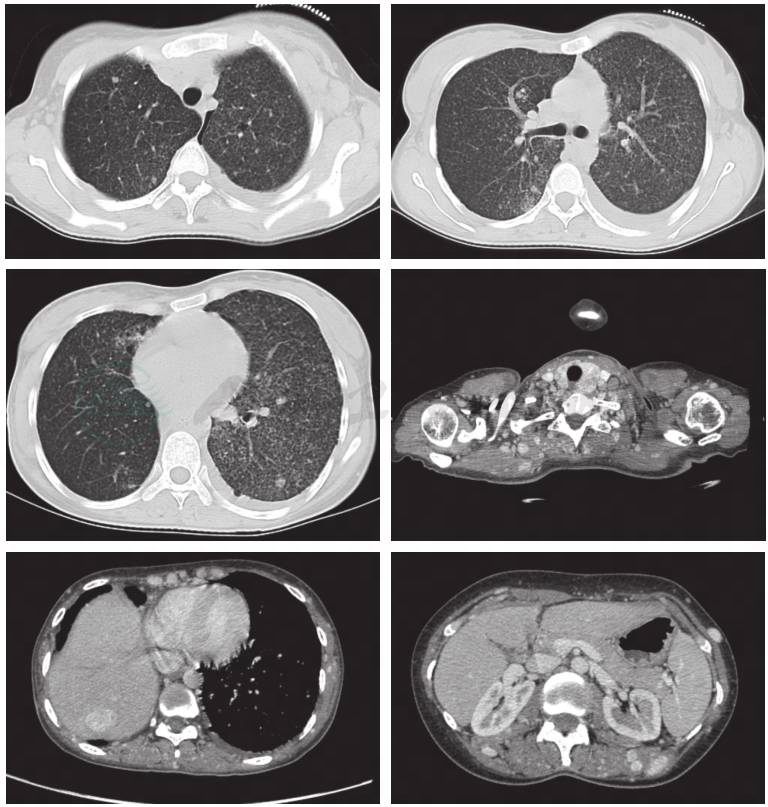

血常规(图3)、尿常规(图4)、粪常规(图5)、血生化(图6)、肿瘤标记物(图7)、感染相关指标(图8)、风湿指标(图9)、胸部平片(图10)、胸部 CT(图11)。

图11 辅助检查(胸部CT2012-1-11)

1.右肺中叶及下叶未见明确显示,请结合临床及病史。

2.双肺多发转移瘤可能。两肺弥漫性小结节,不除外粟粒性肺结核,请结合临床。

3.甲状腺左叶肿块,建议进一步检查。

4.左侧少量胸水,左侧少量气胸。

5.颈部、腋窝、胸背部软组织内异常强化结节,转移瘤可能,请结合临床。

6.胸椎、左侧肱骨头内结节,转移瘤可能,请结合临床。